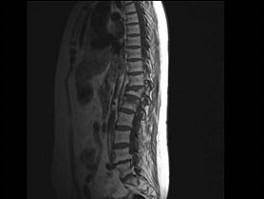

问题 男,65岁,背痛半月余,请结合影像学检查,选出最可能的诊断 ( )

选项 A、骨质疏松性椎体骨折 B、脊椎退行性变 C、脊柱转移瘤 D、化脓性脊柱炎 E、脊椎结核

答案 A